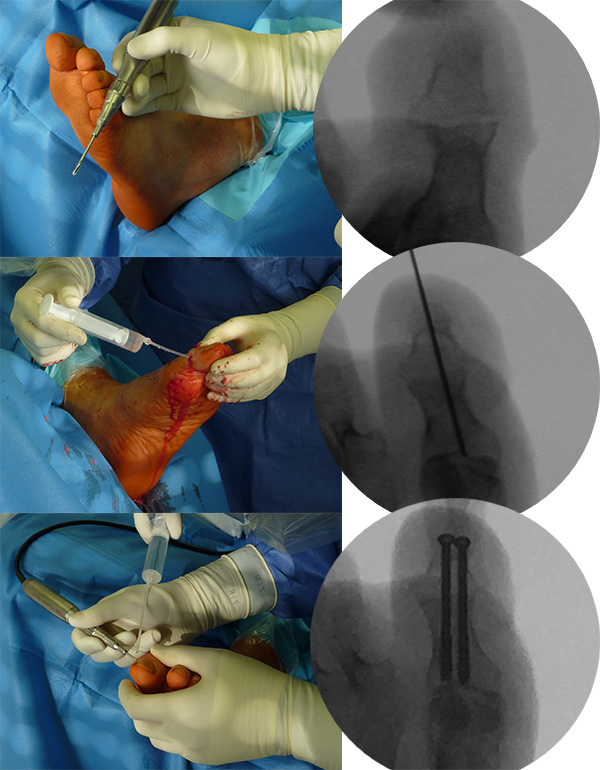

Zur Korrektur der Fehlstellung und zur Ulkus-Behandlung kann in minimalinvasiver Technik über ein mediales Portal eine Walzenfräse in das Interphalangealgelenk eingebracht werden. Über ein zweites laterales Portal wird nach Resektion der Gelenkflächen der Knochenabrieb ausgespült. Sobald ausreichend Knochen reseziert ist, kann die Zehe gestreckt werden. Die beiden abgetragenen Knochenflächen werden im Sinne einer IP-Arthrodese aufeinandergestellt. Es erfolgt dann die Transfixation der Arthrodese mittels ein bis zwei, über die Spitze der Endphalanx eingebrachten Zugschrauben. Problematisch ist es, wenn sich an dieser Stelle unverändert ein Ulkus befindet. In diesem Falle ist die Transfixation der Arthrodese mit zwei perkutan eingebrachten, schräg verlaufenden Kirschner-Drähten weniger risikoreich. Der Eintrittspunkt der K-Drähte befindet sich hier medial und lateral im Bereich der Endphalanx. Bei persistierender Fehlstellung kann je nach Vorspannung eine Tenotomie der EHL- und/oder der FHL-Sehne durchgeführt werden. Normalerweise entspannt sich die Sehne durch die Knochenresektion und den damit verbundenen Längenverlust ausreichend. Zur Korrektur der Fehlstellung „wird die Knochenlänge an die Sehnenlänge angepasst“.

Zum Lesen der Bildbeschreibung und zur Vollansicht bitte die Bilder anklicken.

Abbildung 5

Abbildung 6

Abbildung 7

Abbildung 8